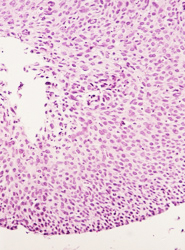

El resultado de una valoración colposcópica de paciente con lesión displásica siempre será confirmado por el estudio histopatológico que realiza el médico anatomopatólogo (estudio de la biopsia tomada en la colposcopía) . A continuación presentamos imágenes histológicas con sus diagnósticos.

• NIC 1 (Displasia leve de cérvix)

• NIC I.- Acantosis regular, anisocitosis y anisocariosis leves. Proceso inflamatorio en la lámina propia severo reactivo.

• NIC I.- No obstante la cariomegalia, la cromatina esta dispuesta en grumos finos.

• NIC I.- Anisocitosis y anisocariosis leves. Estroma ricamente vascularizado.